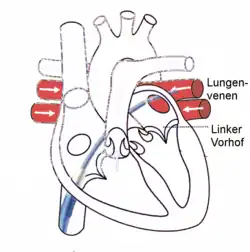

Radiofrequency energy is used in heart tissue or normal parts to destroy abnormal electrical pathways that are contributing to a cardiac arrhythmia. It is used in recurrent atrial flutter (Afl), atrial fibrillation (AF), supraventricular tachycardia (SVT), atrial tachycardia, Multifocal Atrial Tachycardia (MAT) and some types of ventricular arrhythmia. The energy-emitting probe (electrode) is at the tip of a catheter which is placed into the heart, usually through a vein. This catheter is called the ablator. The practitioner first "maps" an area of the heart to locate the abnormal electrical activity (electrophysiology study) before the responsible tissue is eliminated. Radiofrequency ablation technique can be used in AF, either to block the atrioventricular node after implantation of a pacemaker or to block conduction within the left atrium, especially around the pulmonary veins. Radiofrequency ablation for AF can be unipolar (one electrode) or bipolar (two electrodes).[22] Although bipolar can be more successful, it is technically more difficult, resulting in unipolar being used more often.[22] But bipolar is more effective in preventing recurrent atrial arrhythmias.[23]